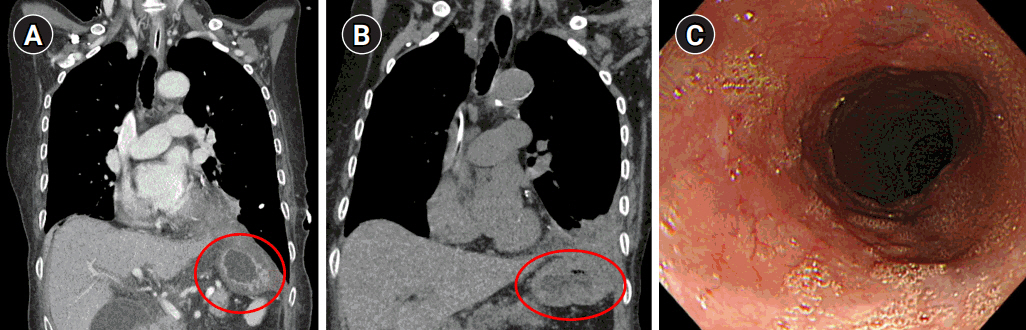

Following surgery, the patient underwent endo-vac therapy and endoscopic stent insertion due to leakage from the esophageal injury site. After approximately three months of nutritional support and conservative care, follow-up CT and EGD showed that there was no herniation and that the perforation site had been sealed with no signs of fistula (Fig. 6).

Fig. 6.Follow-up computed tomography at postoperative day 17 (A) and 3 months (B), showing no herniation of the stomach and bowel contents (circles). (C) Esophagogastroduodenoscopy finding at postoperative 3 months, showing no clear trace of the previous perforation site.